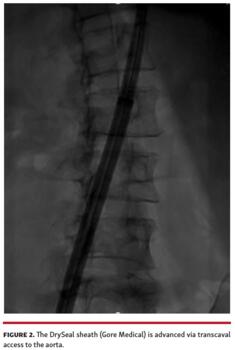

Given the proximity of the thrombus to the left subclavian, bilateral cerebral embolic protection was performed with 2 Sentinel cerebral embolic protection devices (Boston Scientific) (Figure 1). We then obtained transcaval access using standard technique (Figure 2) and a 26 Fr DrySeal sheath was placed across the retroperitoneum into the abdominal aorta. A 17 Fr cannula (Edwards Lifesciences) was placed into the contralateral vein to serve as the AngioVac return cannula. A 180° Gen 3 AngioVac catheter was then prepped in standard fashion and advanced through the 26 Fr DrySeal sheath; it was then engaged with transesophageal echocardiography guidance in the aortic thrombus, and the mobile part was successfully aspirated (Figure 3 and Video 2) with small residual clot that was adherent to the aortic wall (Video 3). The patient was discharged on therapeutic warfarin.